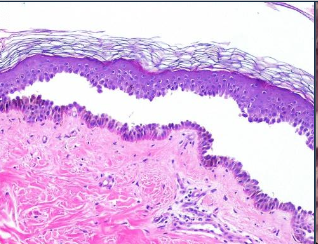

What is Vesiculo-bullous Disease look like histologically?

What is acantholysis in Pemphigus Vulgaris?

Epithelial cell separation “INTRA-EPITHELIAL”

Biopsy and Direct immunofluorescence (DIF)- INTRA-EPITHELIAL separation